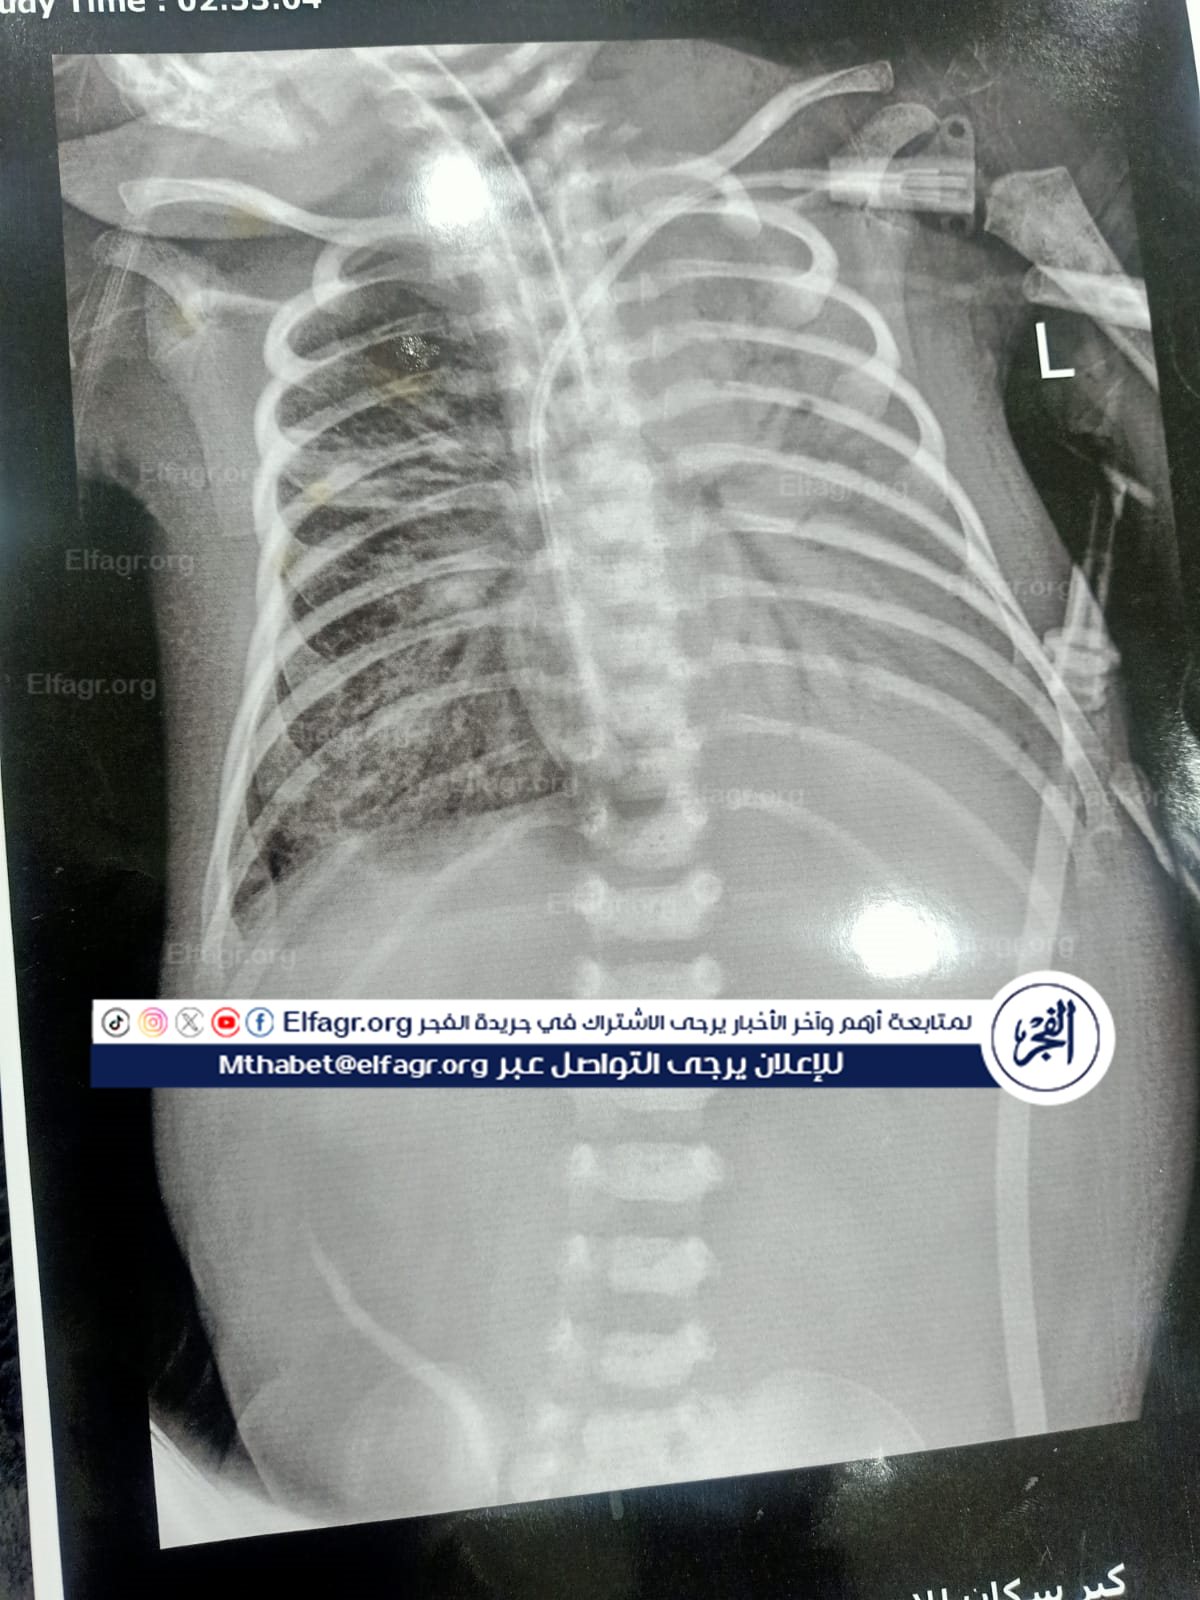

وصفت الأم الحزينة حالة الطفل الرضيع قائلة إن رئة الطفل "أدم" كانت تعمل بشكل جيد منذ ١٥ يناير ٢٠٢٤ حتى ١٩ يناير ٢٠٢٤، وعندما سألت عن الأشعة التي تدل على تدهور حالة الصغير والتي أدت إلى وضعه على جهاز التنفس الصناعي، أخبروها أنهم فقدوا الأشعة.

“أنبوية حنجرية خطأ”.. وتواصل الأم المكلومة في حديثها، أن الأطباء بداخل المستشفى الخاص قاموا بعدة أخطاء طبية، ومن بينها قيام الطبيب "أ.ج" بتركيب أنبوبة حنجرية للطفل خطأ، ما أدى إلى تورم بالحنجرة وأدى إلى تدهور الحالة الصحية وحدوث توقف لعضلة القلب أكثر من مرة كذلك، وقام الطبيب "ع.ه" بتركيب أنبوية حنجرية للصغير بالخطأ مما أدى إلى تلف الرئة الشمال، التي أدت إلى وفاة الطفل بتاريخ ٢٠٢٤/٢/١٣، بالإضافة إلى ترکیب قسطرة سرة في الرقبة، تركيب رايل تغذية بطريقة خطأ مما أحدث نزيفا.